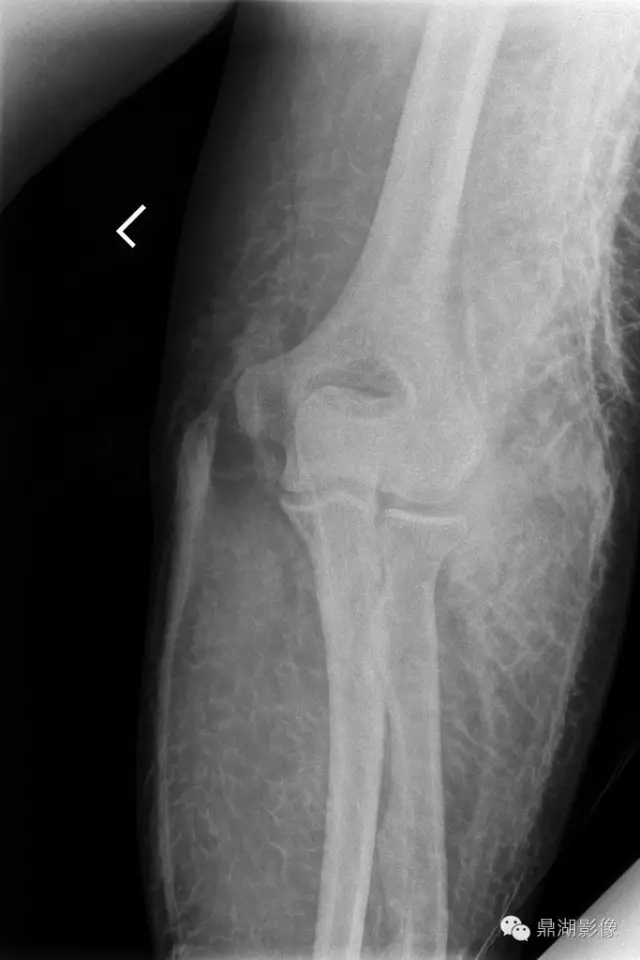

再给大家看一个病例:

50岁,女;非小细胞肺癌( IIB );

CT增强扫描为观察是否复发或转移,注射造影剂时,发生造影剂外渗,约100ml。